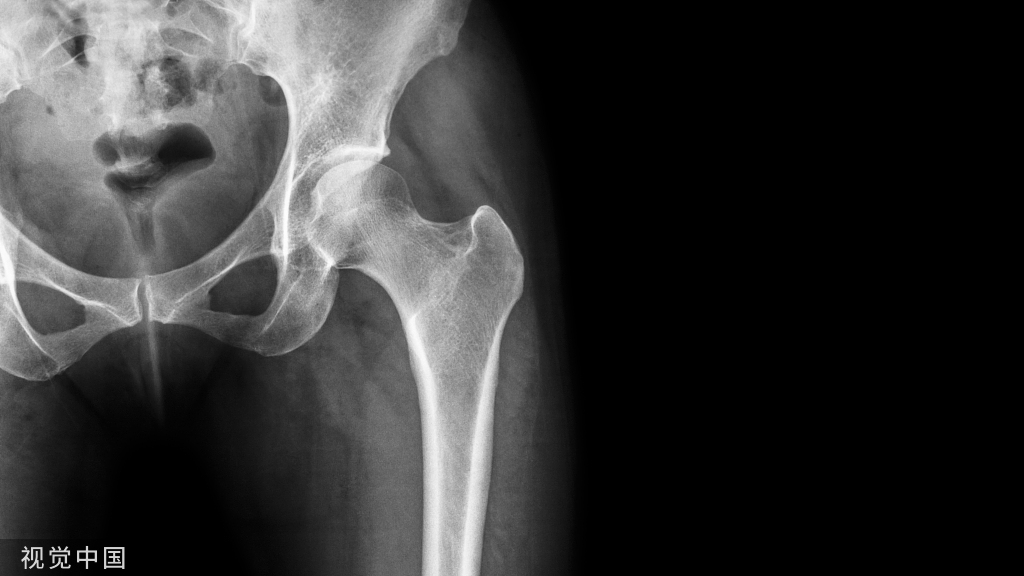

长时间使用TPA或者使用颌内支抗关间隙,容易造成第一磨牙和第二磨牙颚侧尖出现台阶,容易造成术后早接触及咬合关系不良

(引用其他病例图片)